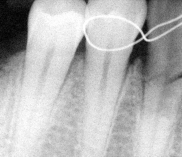

Chirurgia dentystyczna zajmuje się leczeniem operacyjnym jamy ustnej, zębów i tkanek otaczających. Znaczna większość zabiegów z zakresu chirurgii stomatologicznej jest wykonywana w znieczuleniu miejscowym .Dental Park jako jeden z nielicznych oferuje również wykonywanie zabiegów pod narkozą. Najpowszechniejszym zabiegiem z zakresu chirurgii stomatologicznej jest usunięcie zęba czyli ekstrakcja, ale chirurgia stomatologiczna to także zaawansowane zabiegi jak implanty czy wyłuszczanie torbieli kości.

Chirurg stomatolog posiada wieloletnie doświadczenie i w swojej karierze spotkał się z najtrudniejszymi przypadkami. W gabinecie wykonywane jest usuwanie zębów w znieczuleniu miejscowym oraz w narkozie co zapewnia całkowicie bezbolesny zabieg. Pracownia stomatologiczna usuwa zęby mądrości, złamane korzenie. Bardzo często naszymi pacjentami są osoby, które usuwają zęby ze wskazań ortodontycznych. Wykonujemy również zabiegi odbudowy kości jako przygotowanie do leczenia implantologicznego. Nasi pacjenci mogą zawsze liczyć na szybką pomoc w przypadku ropnia, ostrego bólu lub urazu. Chirurg stomatolog zajmuje się wszystkimi nawet najbardziej skomplikowanymi przypadkami.

- resekcje wierzchołka korzenia zęba